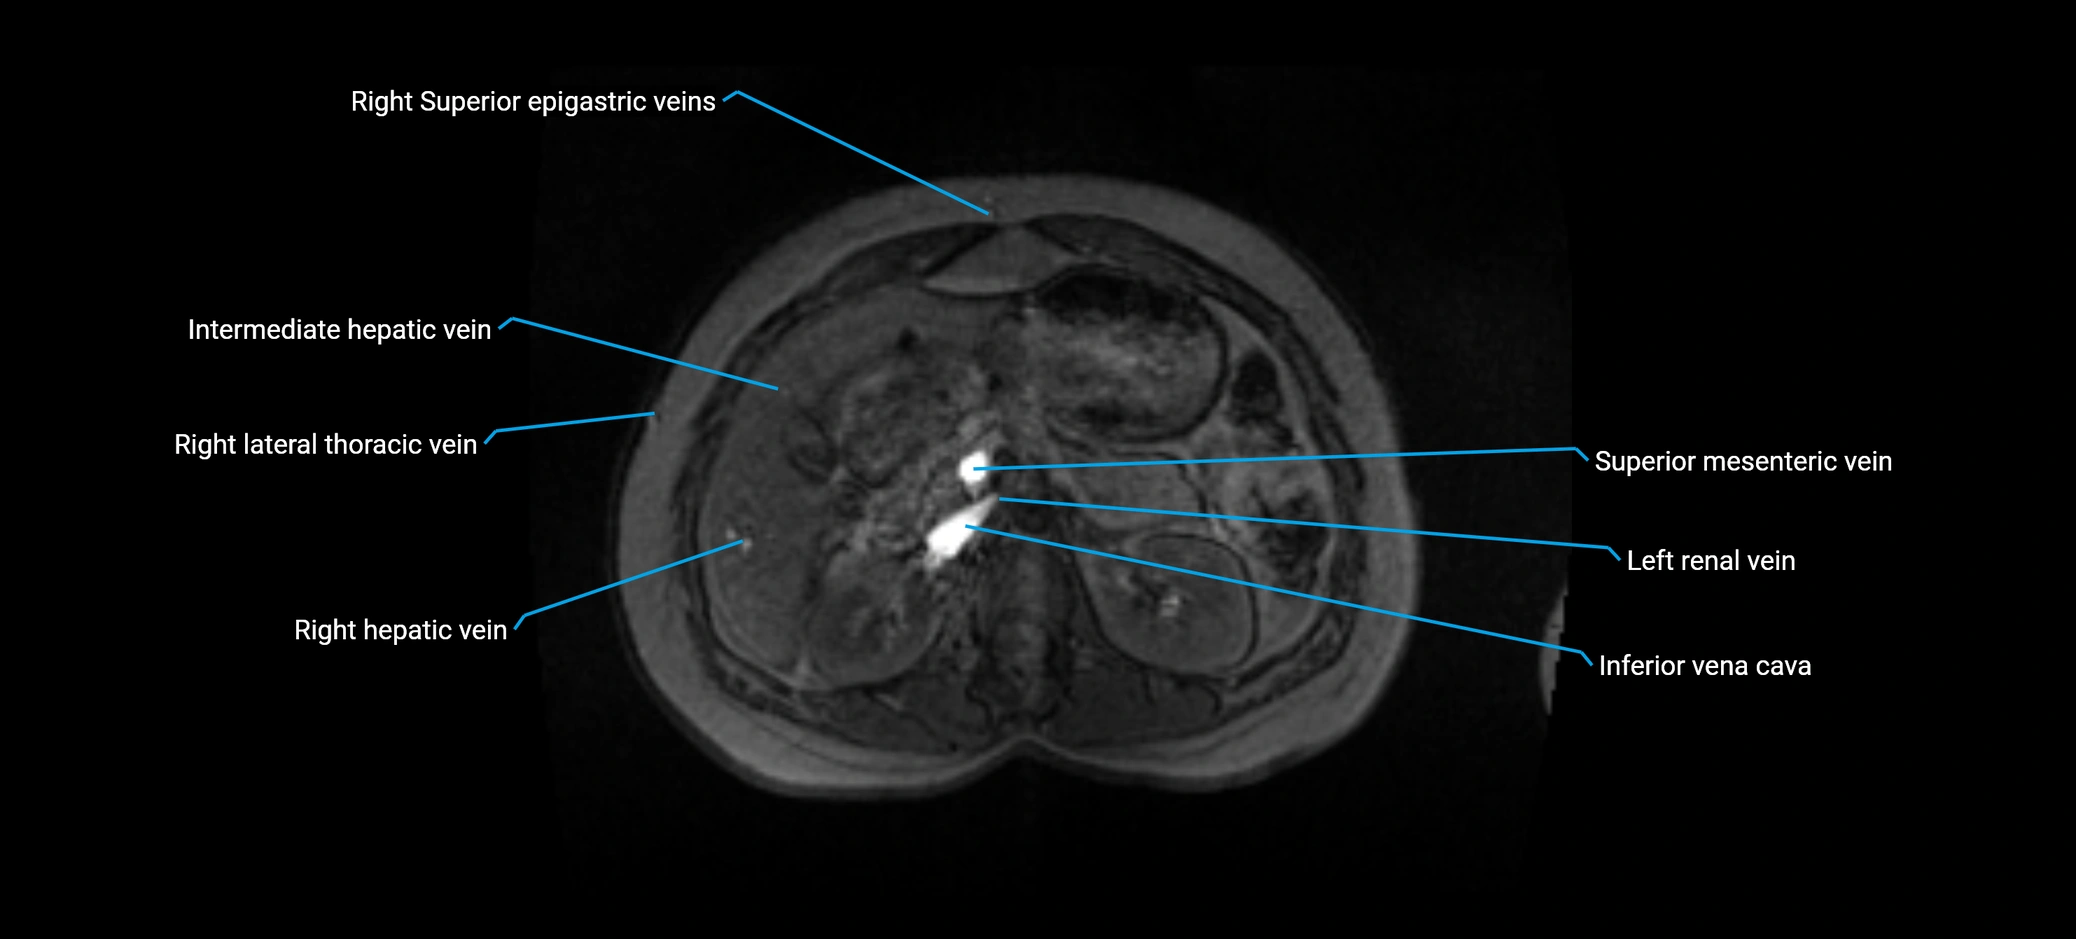

MRI image

image